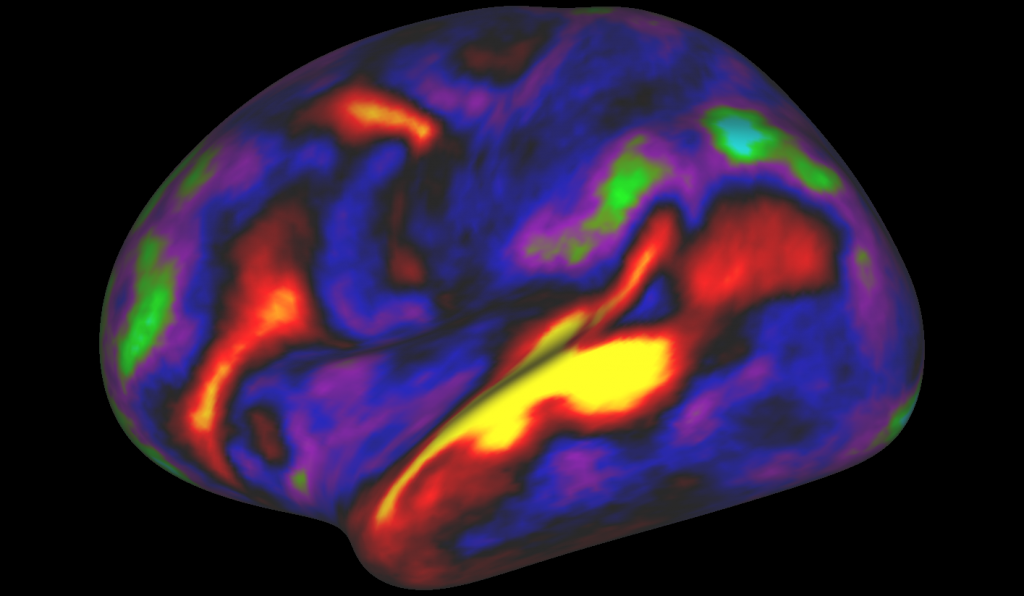

Sur la nouvelle cartographie obtenue, différentes aires du cerveau sont associées à un code couleur : le bleu correspond à la vision, le rouge correspond à l’audition, le vert correspond aux capacités motrices et sensorielles. Et déjà, des observations peuvent être faites. “Il n’y a pas de frontière nette entre ce qui apparaît en bleu et ce qui apparaît en vert. On observe plutôt des transitions graduelles, ce qui indique qu’il existe un entremêlement et une coordination entre différentes modalités sensorielles et différents domaines cognitifs”, remarque ainsi David Van Essen, membre de l’équipe de chercheurs, dans Vice.